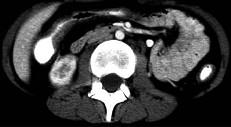

问题 女,32岁,腹痛、腹泻、便秘交替出现,粘液血便半年,里急后重,影像检查如图,最佳的诊断是 ( )

选项 A、溃疡性结肠炎 B、肠结核 C、慢性结肠炎 D、过敏性结肠炎 E、结肠癌

答案 A